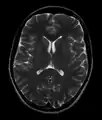

This axial T2-weighted (CSF white) MR scan shows a normal brain at the level of the lateral ventricles.